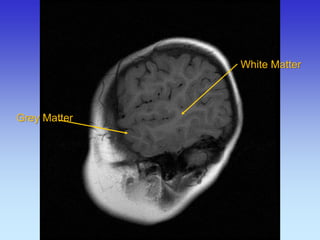

Grey Matter

Superior Sagittal Sinus

White Matter

Grey Matter White Matter